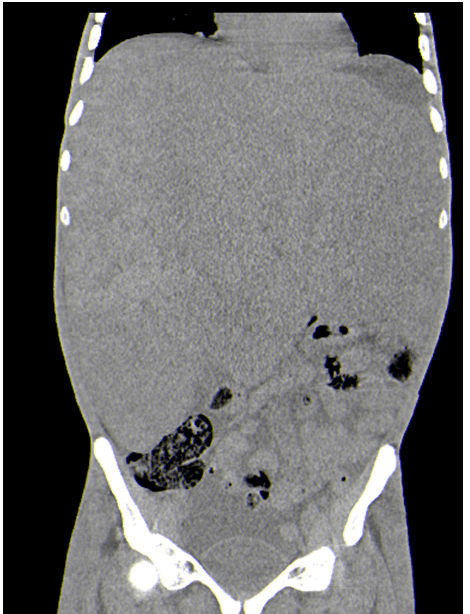

The patient was able to follow-up with oncology and was begun on chemotherapy, specifically carboplatin and etoposide for two cycles. At that point the patient was readmitted and had a follow-up CT scan of the abdomen and chest (Figure 2) and (Figure 3), which showed worsening of his disease. The patient continued to deteriorate and succumbed to the disease six months after diagnosis.

Figure 2: Follow up computed tomography scan of the abdomen. This CT of the abdomen done two months later showing enlargement of the liver mass where it now occupied the majority of the abdominal cavity.